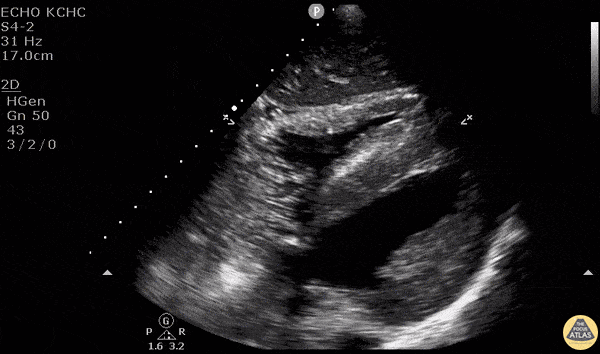

A central venous catheter was placed in the right internal jugular under ultrasound guidance and subxiphoid view was obtained. Saline was rapidly flushed through the brown port and turbulent saline can be seen traveling through the right side of the heart. - Dr. Matthew Riscinti and Dr. Isaac Gordon - Kings County Emergency Medicine